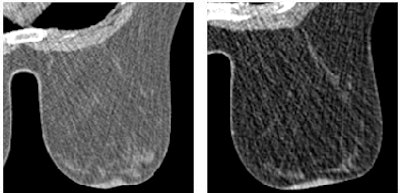

![]() |

| Forty-six-year-old woman with nonspecific inflammatory tissue in right breast. Dynamic MDCT scans at baseline (left) and one minute after contrast administration (right) show thickened homogeneous tissue beneath the nipple, which exhibited strong enhancement. |